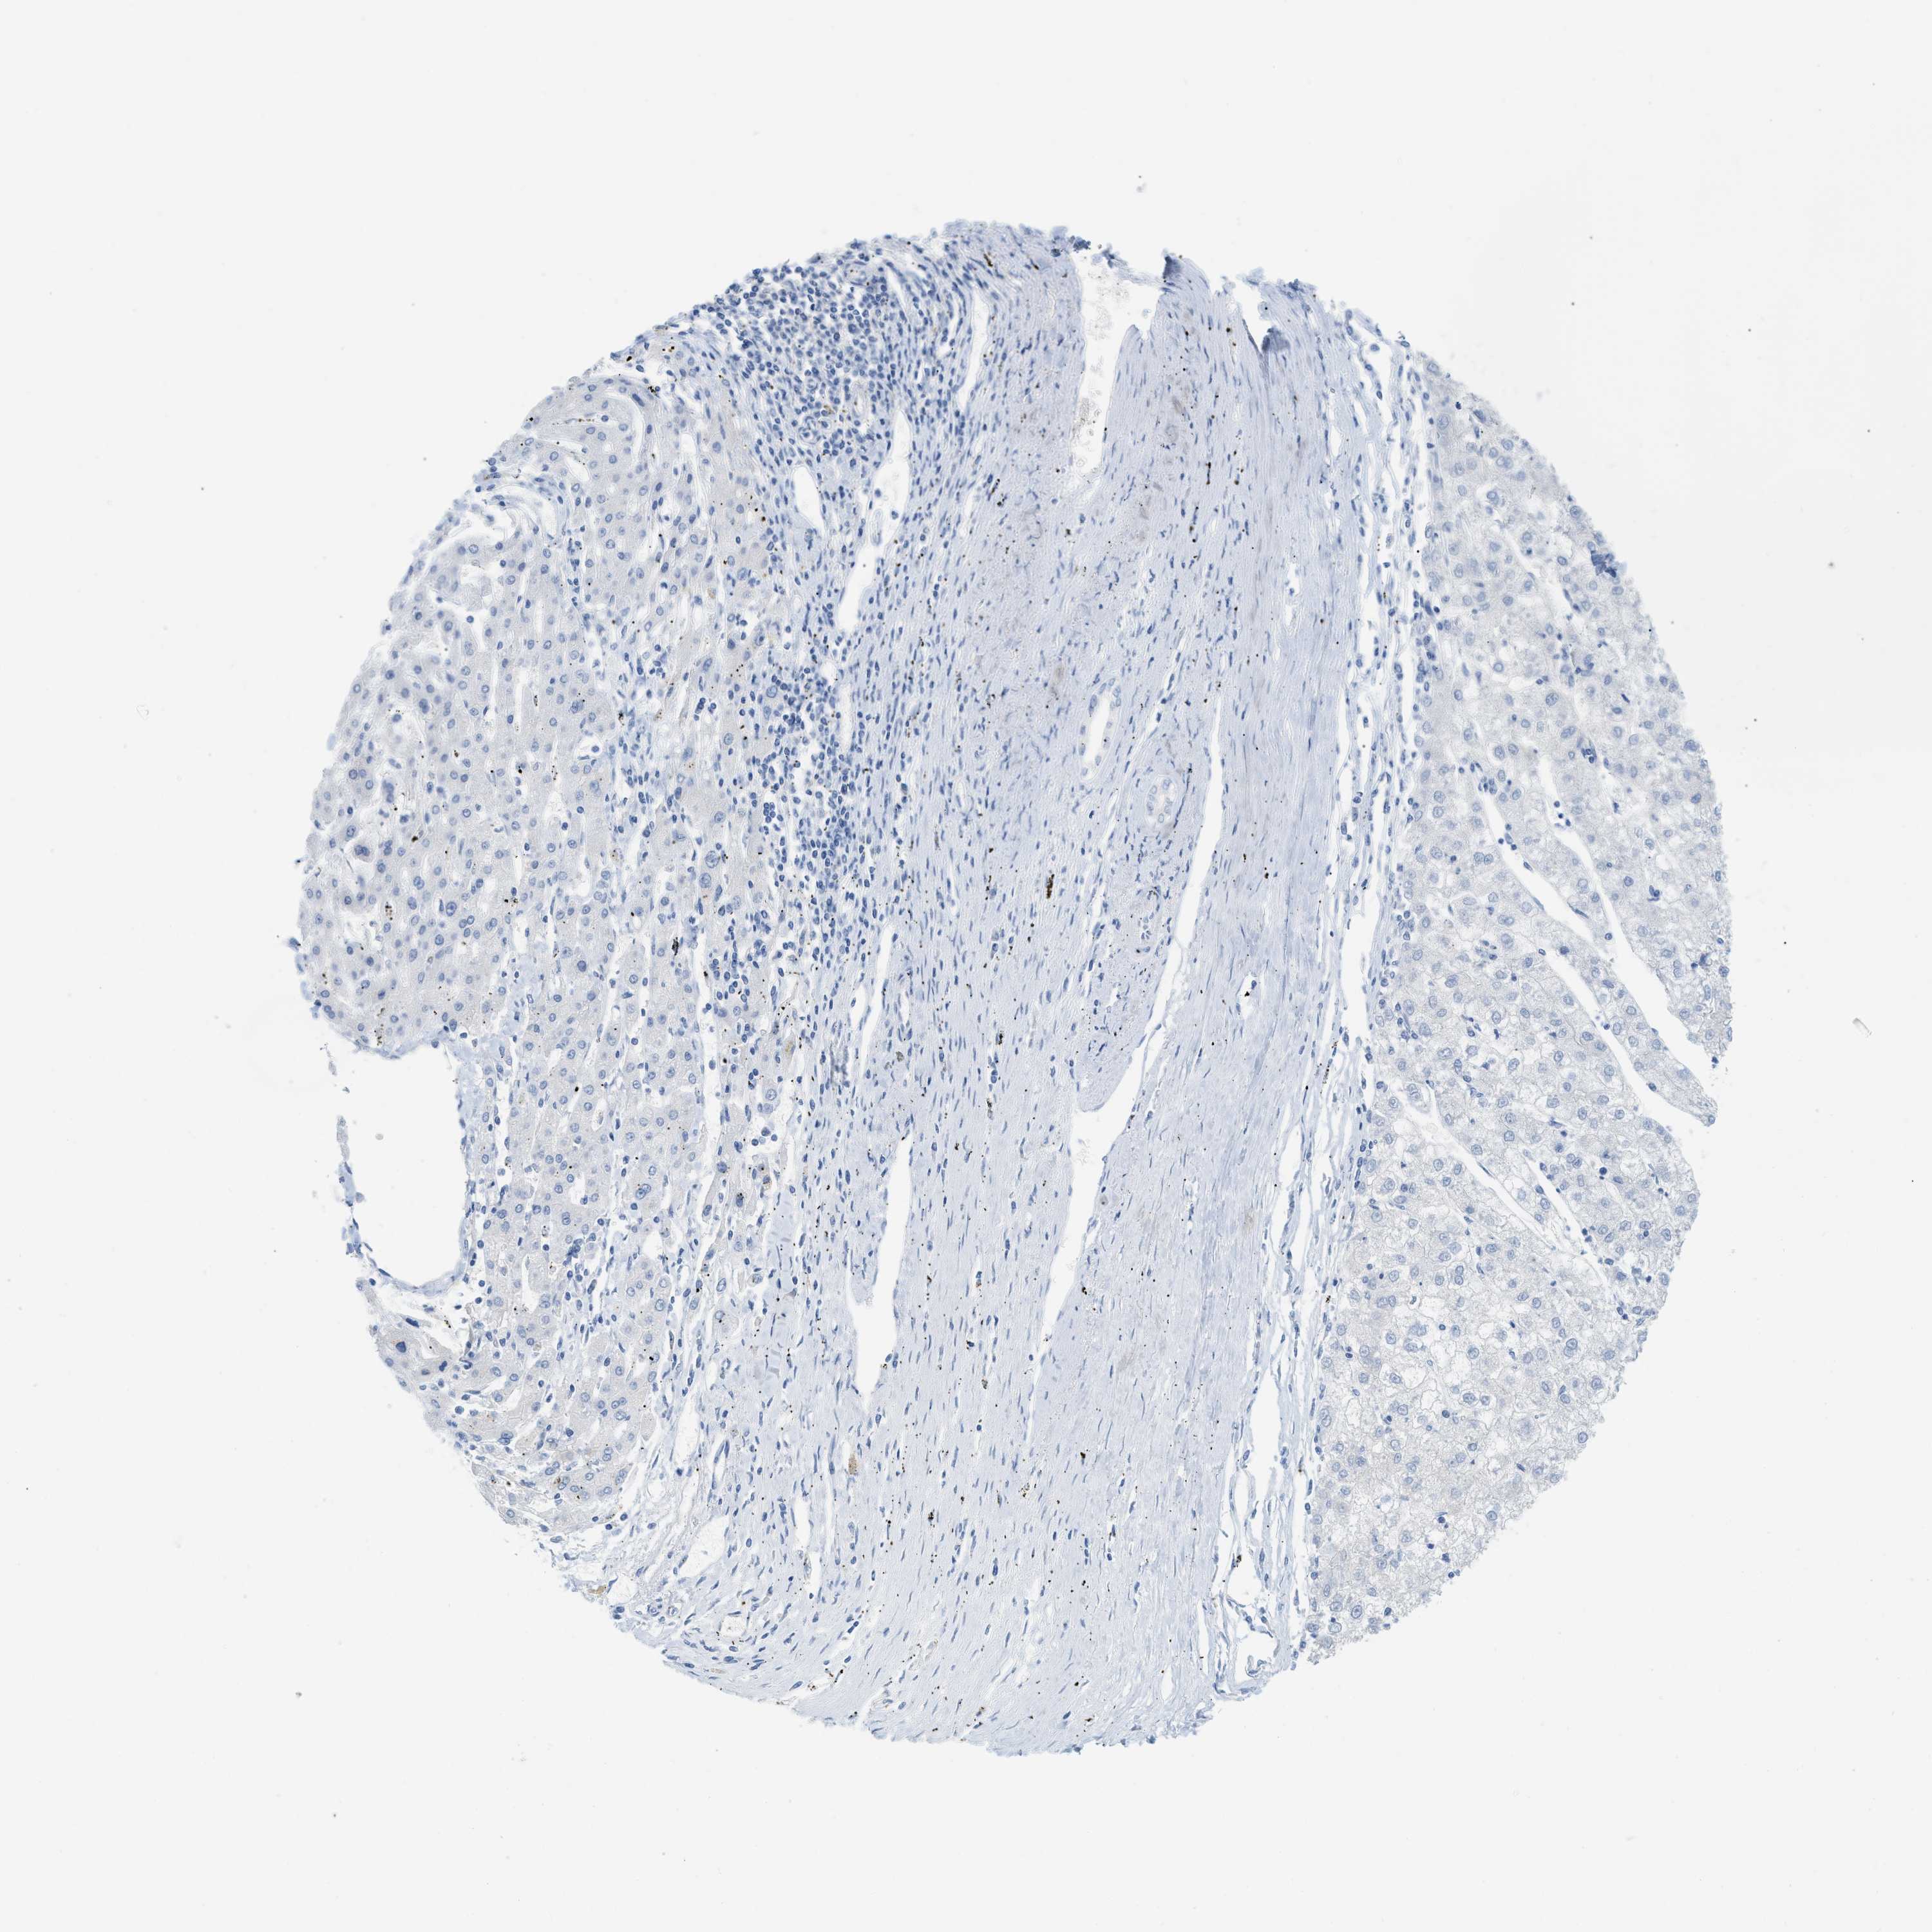

LIVER CANCER - Protein expressioni

A mouse-over function shows sample information and annotation data. Click on an image to view it in a full screen mode. Samples can be filtered based on level of antibody staining by selecting one or several of the following categories: high, medium, low and not detected. The assay and annotation is described here.

Note that samples used for immunohistochemistry by the Human Protein Atlas do not correspond to samples in the TCGA dataset.

Antibody stainingi

Antibody staining in the annotated cell types in the current human tissue is reported as not detected, low, medium, or high, based on conventional immunohistochemistry profiling in selected tissues. This score is based on the combination of the staining intensity and fraction of stained cells.

Each image is clickable and will lead to virtual microscopy that enables deeper exploration of all samples and also displays staining intensity scores, fraction scores and subcellular localization as well as patient and tissue information for each sample.

Antibody HPA001667

Antibody CAB016724

Staining

High

Medium

Low

Not detected

Intensity

Strong

Moderate

Weak

Negative

Quantity

>75%

75%-25%

<25%

None

Location

Nuclear

Cytoplasmic/membranous

Cytoplasmic/membranous,nuclear

Cholangiocarcinoma

Carcinoma, Hepatocellular, NOS